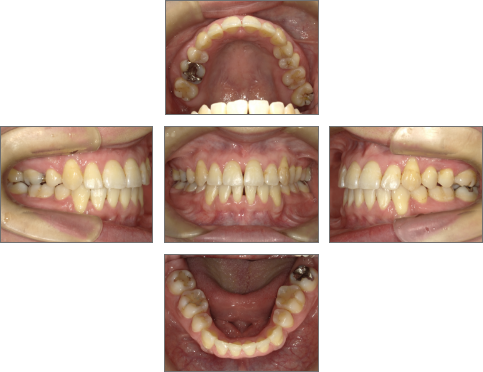

【治療後】

●主訴

歯並びのガタガタが気になる。歯磨きがしづらく、将来、歯が悪くなってしまうのではないか、心配。

●診断名あるいは主な症状

叢生

●年齢

31歳2ヶ月

●治療に用いた主な装置

セラミックブラケット

●抜歯部位

右上4番、左上6番、右下4番、左下4番・8番(親知らず) 計5本抜歯

●治療期間

約2年